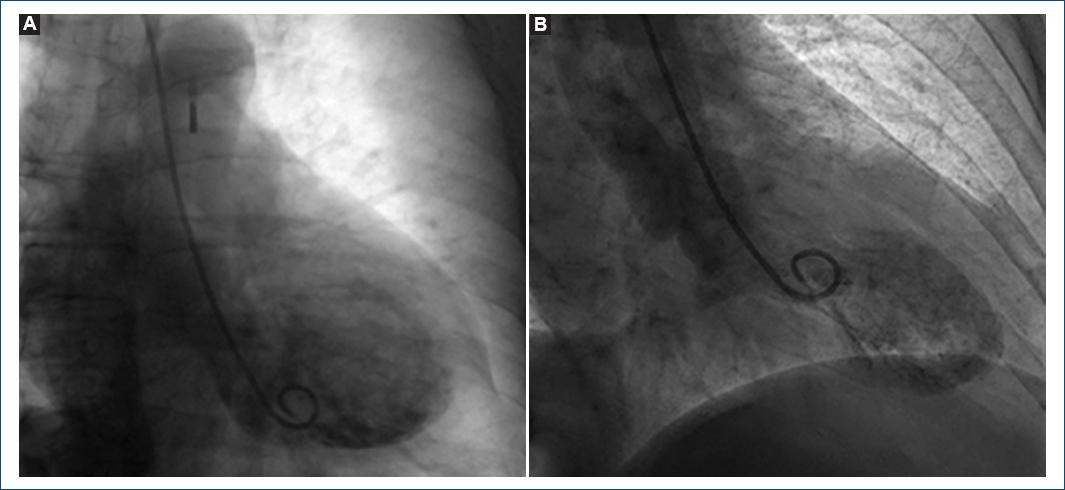

Figure 1 Left ventriculography A: during diastole and B: systole showing typical left ventricular apical ballooning.

This is the case of a 68-year-old woman with a 4-month history of total thyroidectomy due to papillary thyroid cancer. Her treatment was levothyroxine, calcium carbonate, and calcitriol. She was transferred to our emergency department with a diagnosis of ST-elevation myocardial infarction. Urgent coronary angiography showed findings of non-obstructive Takotsubo syndrome (TTS) (Fig. 1A and B). Due to signs of cardiogenic shock, she was started on dobutamine and norepinephrine, and an intra-aortic balloon pump (IABP) was placed. Here, we present a rare presentation of TTS and dilated cardiomyopathy due to severe hypocalcemia.